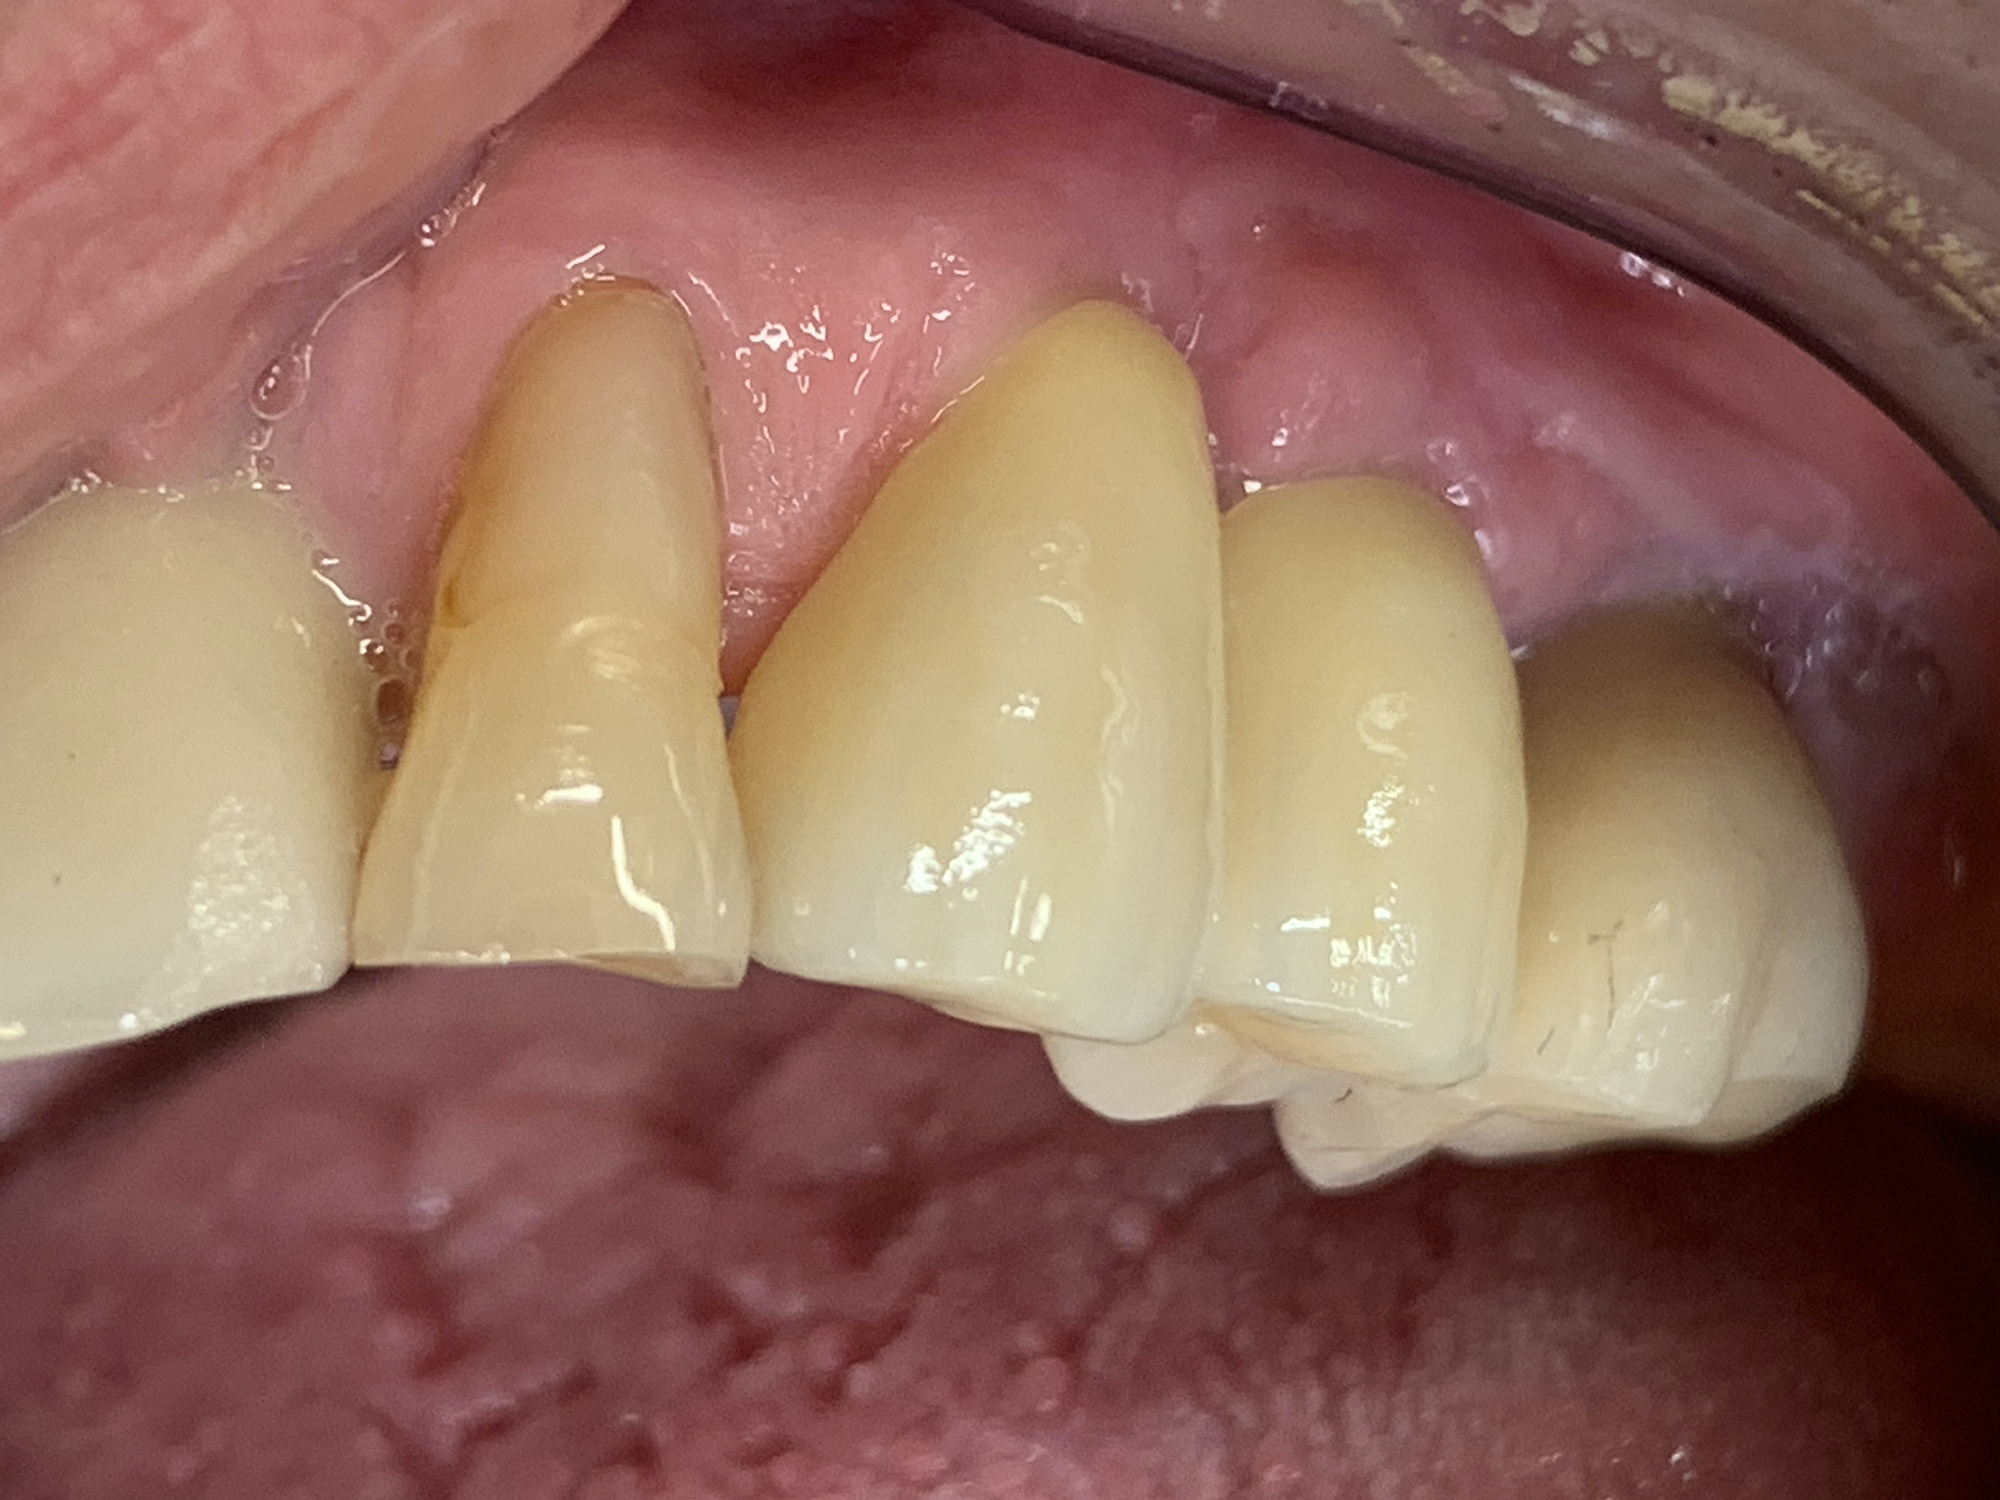

Keramikimplantate

Wir setzen auf hochwertige Keramikimplantate von Swiss Dental Solutions. Diese sind metallfrei, ästhetisch, verträglich und lassen sich oft in nur einer Sitzung einsetzen – für ein natürlich schönes Lächeln.

• Die helle Farbe im Vergleich zu den schwarzgrauen Titanimplantaten garantiert ein natürliches Lächeln und eine herausragende Ästhetik

Vorteile Keramik Implantate

• Weiß

• metallfrei

• immunologisch neutral

• biokompatibel

• hochästhetisch

• keine Periimplantitis